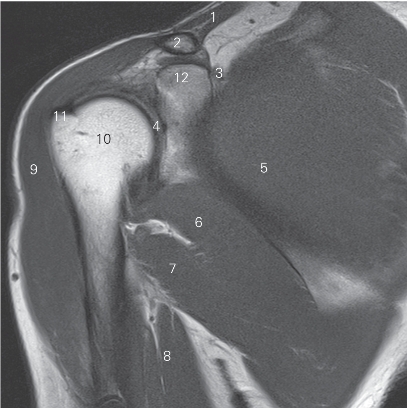

图4-22 经肩关节盂的矢状断层MR T2WI FS

1 锁骨 clavicle 2 冈上肌 supraspinatus

3 肩胛冈 spine of scapula 4 冈下肌 infraspinatus

5 小圆肌 teres minor 6 三角肌 deltoid

7 肱三头肌长头 long head of triceps brachii

8 大圆肌 teres major

9 腋窝血管神经束 axillary neurovascular bundle

10 关节盂 glenoid cavity 11 胸小肌 pectoralis minor

12 胸大肌 pectoralis major

13 喙突下滑囊 bursa mucosa of inferior coracoid pocess

14 喙突 coracoid prcess